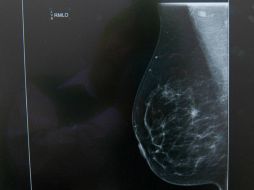

Suplementos Cáncer de mama tiene en hombres mismos síntomas que mujeres 23 de octubre de 2015 - 17:34 hs Cáncer de mama Calor de hogar

Tecnología Jóvenes mexicanos desarrollan 'app' para detectar cáncer de mama 22 de octubre de 2015 - 18:04 hs Ciencia médica Cáncer de mama

Tecnología Patentan fármaco que reduce cáncer de mama, colon y melanoma 20 de octubre de 2015 - 07:53 hs Ciencia médica Enfermedades